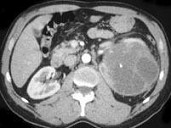

- 单项选择题女,48岁, 左腰部胀痛不适2月余,根据所示图像, 最可能的诊断是 ( )

A、左侧囊性肾癌

B、左侧肾囊肿

C、左侧多囊肾

D、左侧肾脓肿

E、左侧肾积水